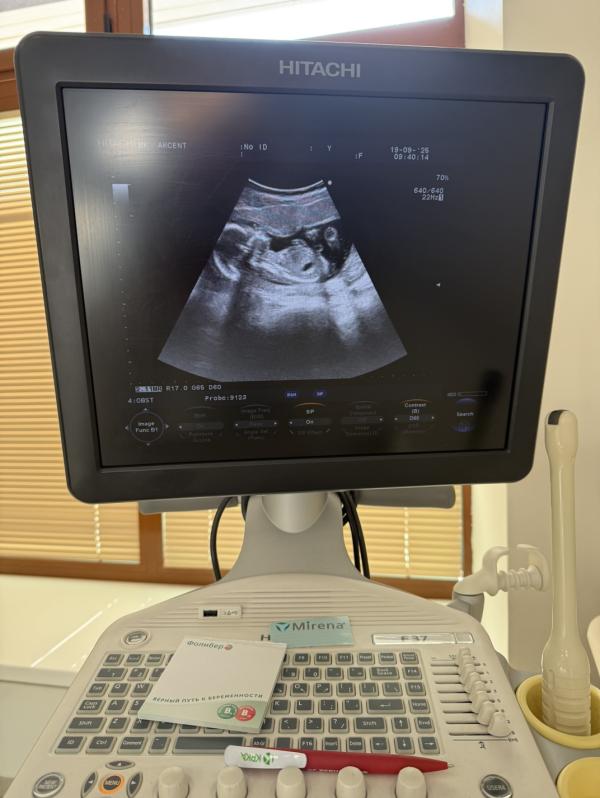

17 недель 2 дня 🔥

Сегодня была на свидании с моим маленьким мужчиной 🥰

Очень активно показывал себя, отворачивался спинкой , бил ножками . Я в каком-то восторге снова , увидев такого большого человека внутри себя 😍